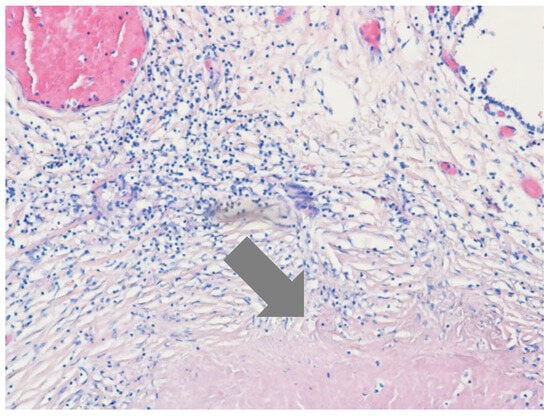

Tuberculous Aneurysm of the Thoracic Aorta: A Diagnostic and Therapeutic Challenge in the Modern Era

Introduction: Tuberculous aneurysm of the thoracic aorta (TBAA) is an extremely rare but potentially fatal manifestation of tuberculosis (TB). Clinical presentation may include hemoptysis in the absence of parenchymal lung abnormalities. Case report: We presented a 62-year-old male with cough, chest pain, [...] Read more.

Introduction: Tuberculous aneurysm of the thoracic aorta (TBAA) is an extremely rare but potentially fatal manifestation of tuberculosis (TB). Clinical presentation may include hemoptysis in the absence of parenchymal lung abnormalities. Case report: We presented a 62-year-old male with cough, chest pain, and minimal hemoptysis. Diagnostic evaluation confirmed an aneurysm of the descending thoracic aorta at a site previously treated with endovascular repair, with no imaging findings suggestive of pulmonary TB. Bronchoscopy revealed blood in the main bronchi without an identifiable endobronchial source. The diagnosis of TB was established by polymerase chain reaction (PCR) testing of bronchial aspirate obtained during bronchoscopy. Emergency surgical intervention was recommended because of an impending aortic rupture, but the patient declined surgery. Standard antituberculous therapy was initiated, and the patient subsequently developed drug-induced liver injury, prompting temporary cessation of treatment. The clinical course was later complicated by the development of an aortoesophageal fistula (AEF), with significant implications for prognosis. Conclusions: Early recognition of TBAA, along with a multidisciplinary approach that integrates advanced diagnostic modalities, timely vascular intervention, and carefully managed antituberculous therapy, is essential to reduce mortality and optimize treatment outcomes. Full article

Show Figures

Figure 1